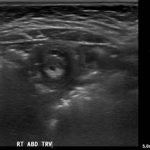

A segment of bowel within the right abdomen that measured approximately 1.6 x 1.5 cm transaxially. It demonstrated a hypoechoic edematous outer loop of bowel (blue arrow) and hyperechoic compressed loop of bowel telescoping within (red star), this is known as the “target sign.”

Intussusception is the invagination or telescoping of part of the intestine into itself. It is the most common cause of intestinal obstruction in children younger than 2 years.1 Ninety-five percent are ileocolic but any part of the small or large intestine can be involved.2 Abdominal pain is the most common symptom.3 Patients classically experience cyclic episodes (10 – 15 minutes) of severe abdominal pain. During these painful episodes, patients are often described as drawing the legs up to the abdomen and screaming in inconsolable pain. Ultrasound is operator dependent, however the sensitivity and specificity for intussusception approaches 100% with an experienced ultrasonographer.4 A good history and physical exam remain important, as the appearance of a “target sign” in the right lower abdomen can also be seen in appendicitis, caused by an appendixwith an appendicolith.